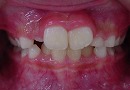

治療前 治療後

この様な歯並びの方はかなり見受けられるとと思われます。

当矯正歯科医院では、咬合バランスを改善する為には、

顎骨の拡大だけでは不十分と考ています。

その為、かみ合わせの高さなど立体的に改善していく事を心がけて日々治療しています。